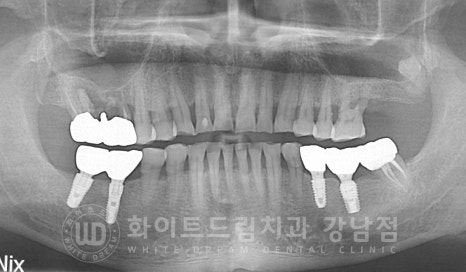

환자분의 초진 X-RAY 사진입니다.

환자분의 X-RAY 사진을 보니 환자분이 불편함을 호소하시는

16, 17번 크라운 주위로 염증이 크게 자리 잡고 있는 것이 확인됩니다.

신경치료를 한 치아이기 때문에 큰 통증은 없지만 심하게 흔들리고 악취가 나는 것 같다고

이야기를 하셨는데요.